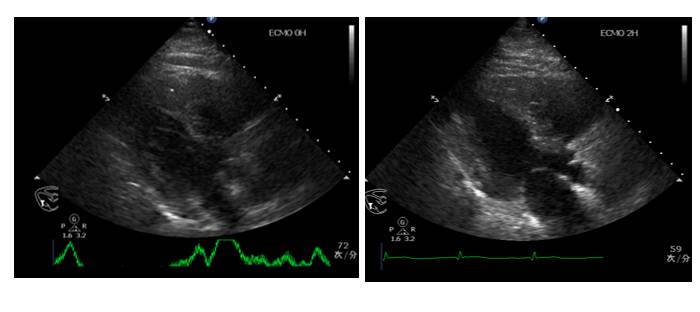

心脏彩超

右:左=1:1

IVC>2.5cm

EF:0.35

♥床边心超提示:心率增快时左心收缩力明显减弱,伴充盈压高,予以艾司洛尔(0.05mg/kg/min)控制心室率后心率降至55左右,血压明显改善,102/70mmHg,复查心超左心收缩舒张功能均改善。